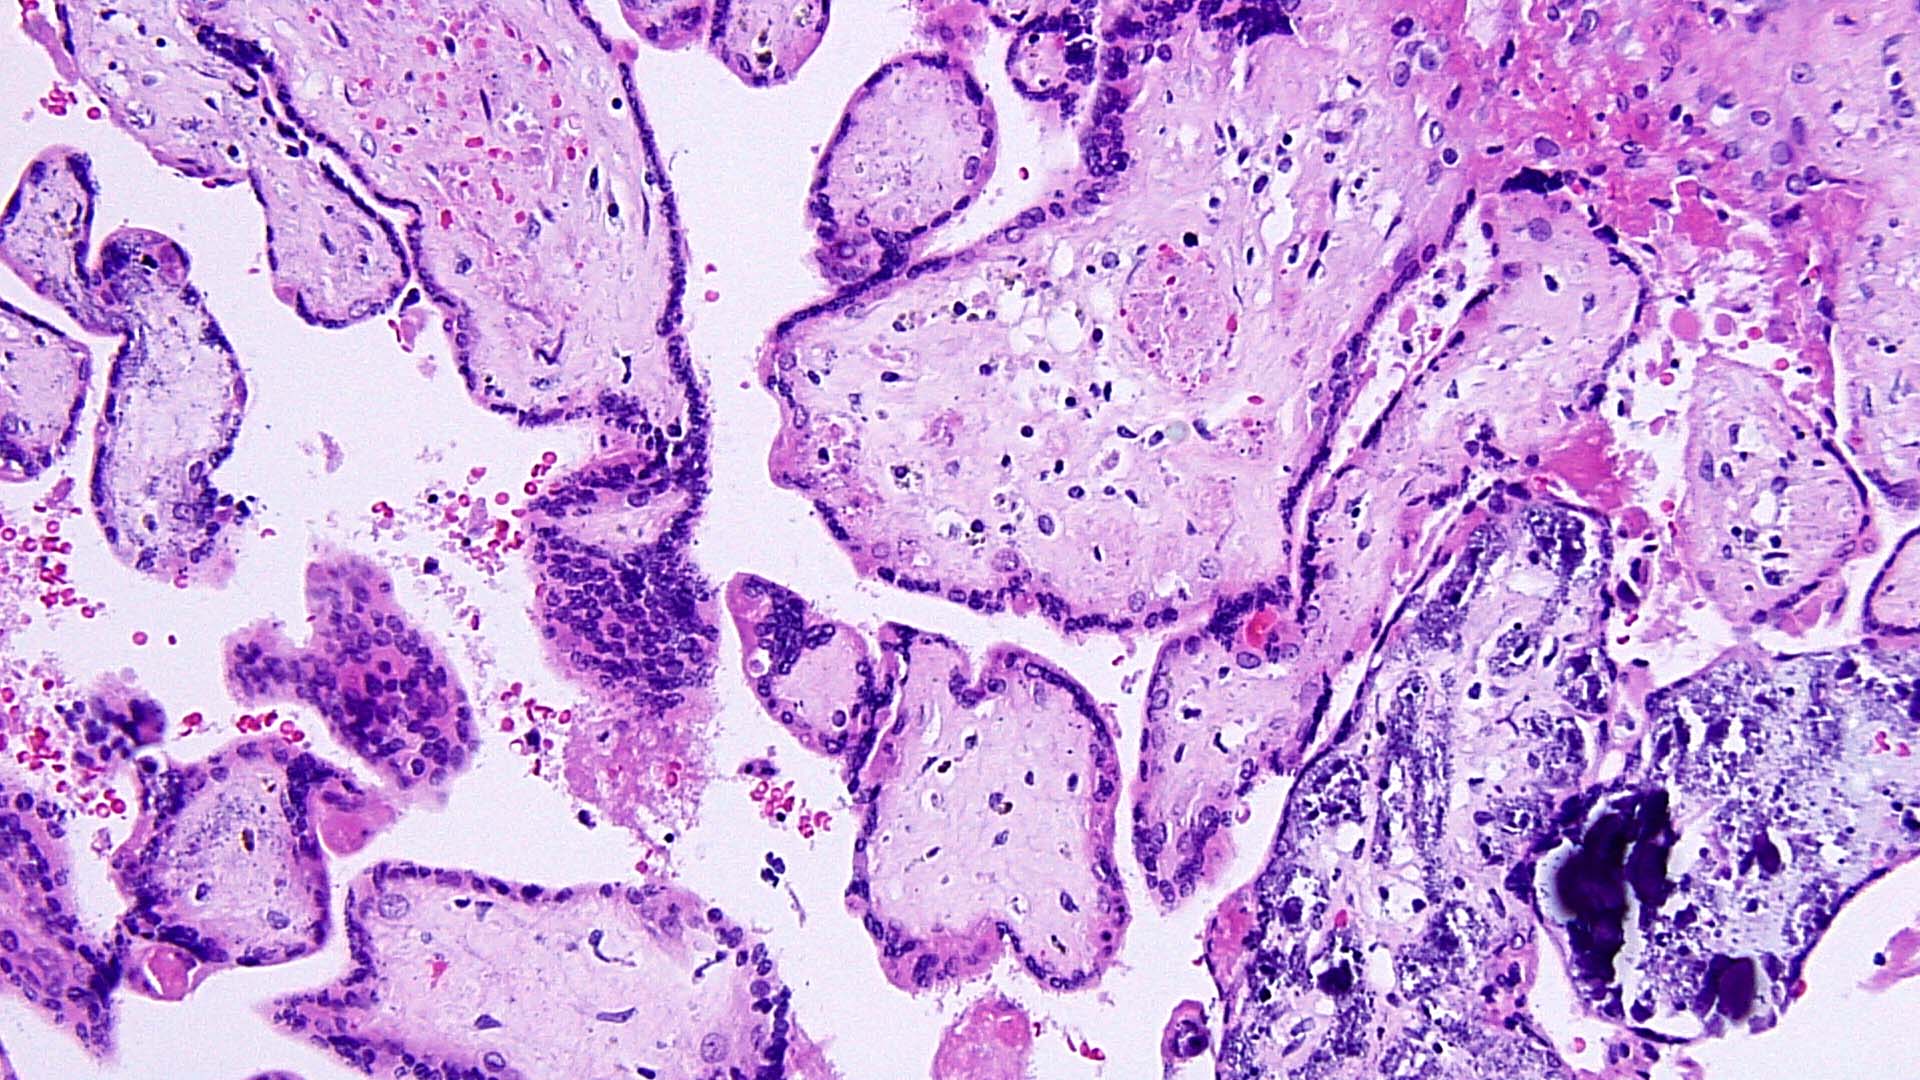

A 28 year old male presents with gross hematuria after a trip abroad. Cystoscopy and...

Resection of a 3.5 cm subcutaneous mass from the left hand of a middle-aged man...